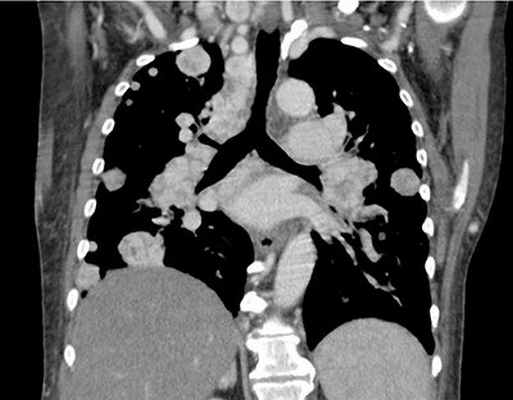

Здесь представлены компьютерно-томографические срезы на разных уровнях. Мы имеем возможность видеть просветы всех бронхов, оценить состояние их стенок и окружающей легочной паренхимы. Для того чтобы лучше оценить характер патологических изменений, возможно использование КТ высокого разрешения.

КТ средостения

Компьютерная томография средостения — это рентгенологическое исследование мягких тканей в области грудной клетки при помощи томографа. Процедура позволяет сделать четкие снимки исследуемой зоны и создавать трехмерную модель органов.

Что показывает КТ средостения

Компьютерная томография дает подробную информацию о состоянии всех тканей, костей и органов в грудной области. Чувствительная методика позволяет определить наличие заболеваний на любом этапе их развития, в том числе и на запущенных стадиях. Особенно полезна процедура в случаях, когда есть подозрение на наличие опухолейлегких, рака костей или туберкулеза, а также других опасных болезней органов грудной клетки.

КТ органов грудной клетки (воспалительные заболевания, опухоли верхних и нижних дыхательных путей на самой ранней стадии заболевания, травмы: повреждения бронхов, травмы грудной клетки)

КТ органов грудной клетки — информативный вид диагностики заболевания сердца, легких, органов средостения, пищевода, лимфатических узлов, мягких тканей. В 40 % случаев КТ позволяет получить информацию, которая обычным рентгенологическим методам не доступна.

- для оценки поражения внутригрудных лимфатических узлов при лимфопролиферативных заболеваниях